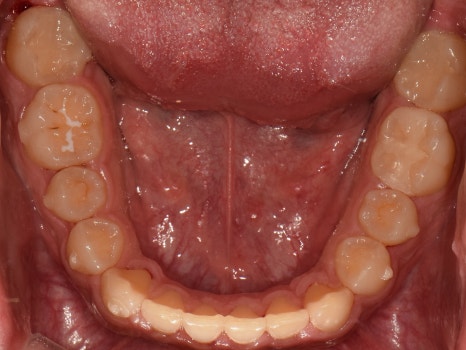

교합면에서 관찰해보면

밖으로 뻗쳐 있던 어금니들도

제 위치를 찾아 돌아온 것을 볼 수 있네요.